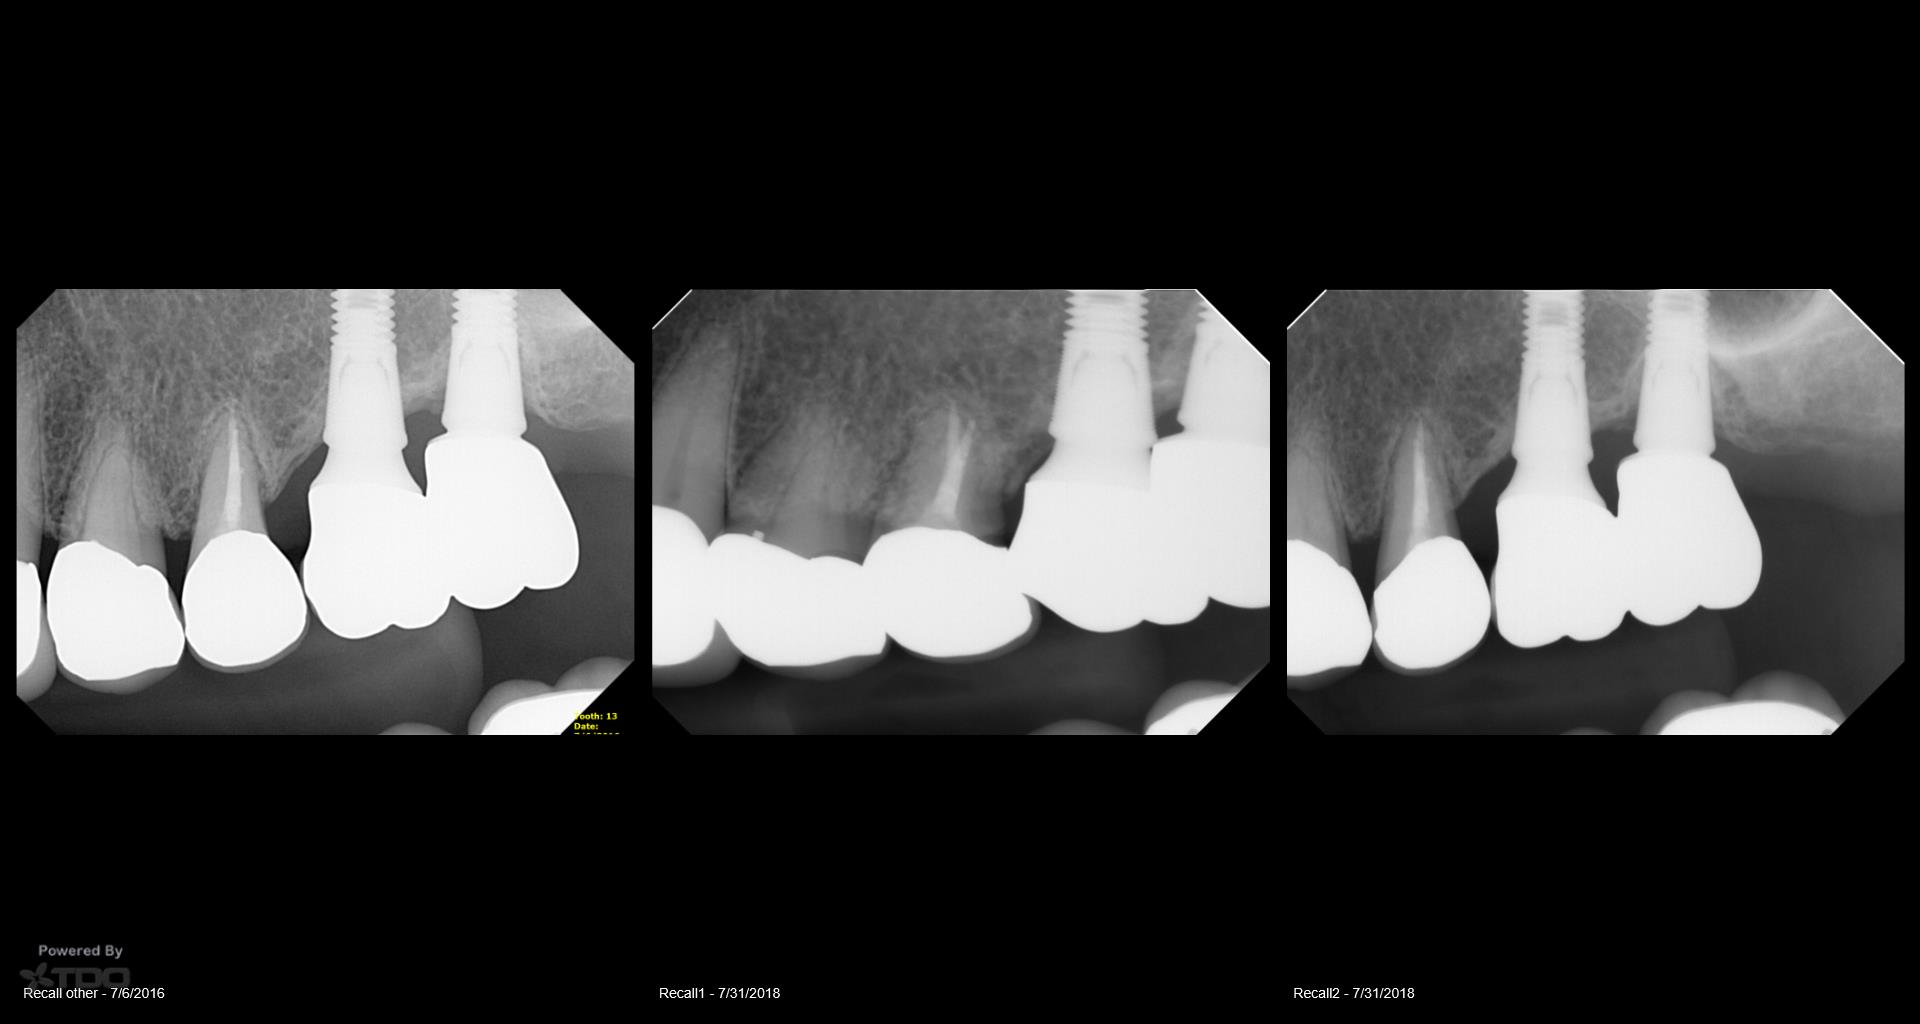

13 years on a tooth which shouldn’t have made it